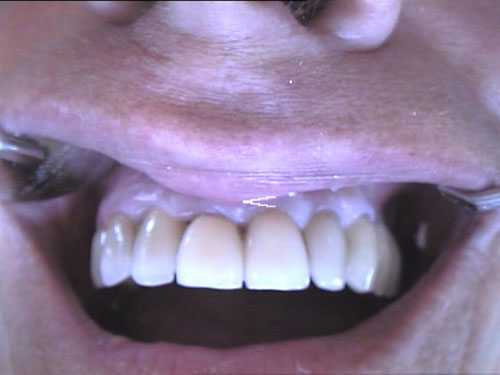

Zahn-Anomalien 1